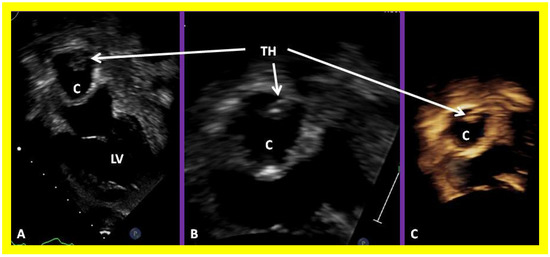

On 2D echocardiography, the atretic tricuspid valve is visualized directly as a dense band of echoes at the site where the tricuspid valve should be, as shown in Figure 4, Figure 5 and Figure 6; this echo appearance is that of the most frequent muscular type of TA. This anatomy is better demonstrated in apical and subcostal four chamber views than in other views. The other anatomic types (Figure 1), namely, membranous, valvular, Ebstein’s, atrioventricular septal defect, and unguarded tricuspid valve with muscular shelf, are rare and may also be recognized on 2D echocardiography. An example of an atrioventricular septal defect type of TA [30] is demonstrated in Figure 7; in this example, a 2D echocardiogram demonstrated an ostium primum ASD with a common atrioventricular valve and a small RV (Figure 7a,b); the entry into the RV appeared to be occluded by a leaflet of the common atrioventricular valve. Left ventricular and right atrial cineangiograms confirmed these findings [30]. Evaluation of the crux cordis (Figure 8) on a 2D echocardiogram (subcostal four chamber view) may help to distinguish the various anatomic types (Figure 1) from each other. In the muscular type of tricuspid atresia, a dense band of echoes is seen where the normal tricuspid valve should be (Figure 8A). In membranous types of tricuspid atresia, a thin membrane is seen instead (Figure 8B). In both these types, the anterior leaflet of the detectable atrioventricular valve is attached to the left side of the interatrial septum (Figure 8A,B). In the atrioventricular septal defect type of tricuspid atresia, the crux cordis is abnormal and cannot be identified; the anterior leaflet of the detectable atrioventricular defect is attached to the anterior wall of the heart, and a large atrioventricular valve leaflet occludes the entry of the RA into the RV (Figure 8C). Based on these observations, it was concluded that 2D echocardiographic (and angiographic) features help to differentiate the atrioventricular canal type of tricuspid atresia from the classic muscular tricuspid atresia cases [30].

Figure 38. Selected video frames showing left ventricle (LV) in diastole (LVD) (A) and in systole (LVS) (B) demonstrating normal ejection fraction (EF) of 63.4%. C, conduit; LA, left atrium.

Applsci 11 09472 g038

Figure 39. Selected video frame from an apical four-chamber view demonstrating the left ventricle (LV), hypoplastic right ventricle (HRV) with an atretic tricuspid valve (ATV) in a patient who had Fontan procedure. Cross-sectional view of the conduit (COND) is also shown. Note small ventricular septal defect (VSD) (long arrow).

Applsci 11 09472 g039

Figure 40. Selected video frames from apical four-chamber views demonstrating unobstructed pathway (UOP) (long arrow) between the right and left (LA) atria; the mitral valve is closed in (A) while it is open in (B). ATV, atretic tricuspid valve; C, conduit; HRV, hypoplastic right ventricle; LV, left ventricle.

Applsci 11 09472 g040